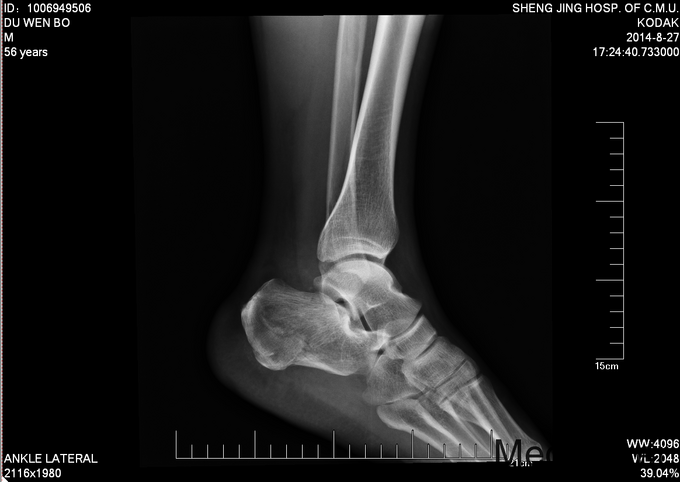

左跟骨骨折sanders2型

患者及其家属自述于2015-10-17 13:30 因在自家干活时不慎从2米高梯子上摔下,当时患者意识清醒,无法站立,左踝部疼痛、肿胀、活动受限,以“左踝部骨折”为诊断收入我科;患者伤来无发热、无头晕、恶心呕吐,无呼吸困难,既往饮食睡眠可,大小便正常; 左踝部肿胀明显,压痛阳性,左踝部活动受限,可闻及骨擦音及骨擦感;患肢皮肤感觉较健侧无明显异常,足趾可活动,足背动脉可触及;